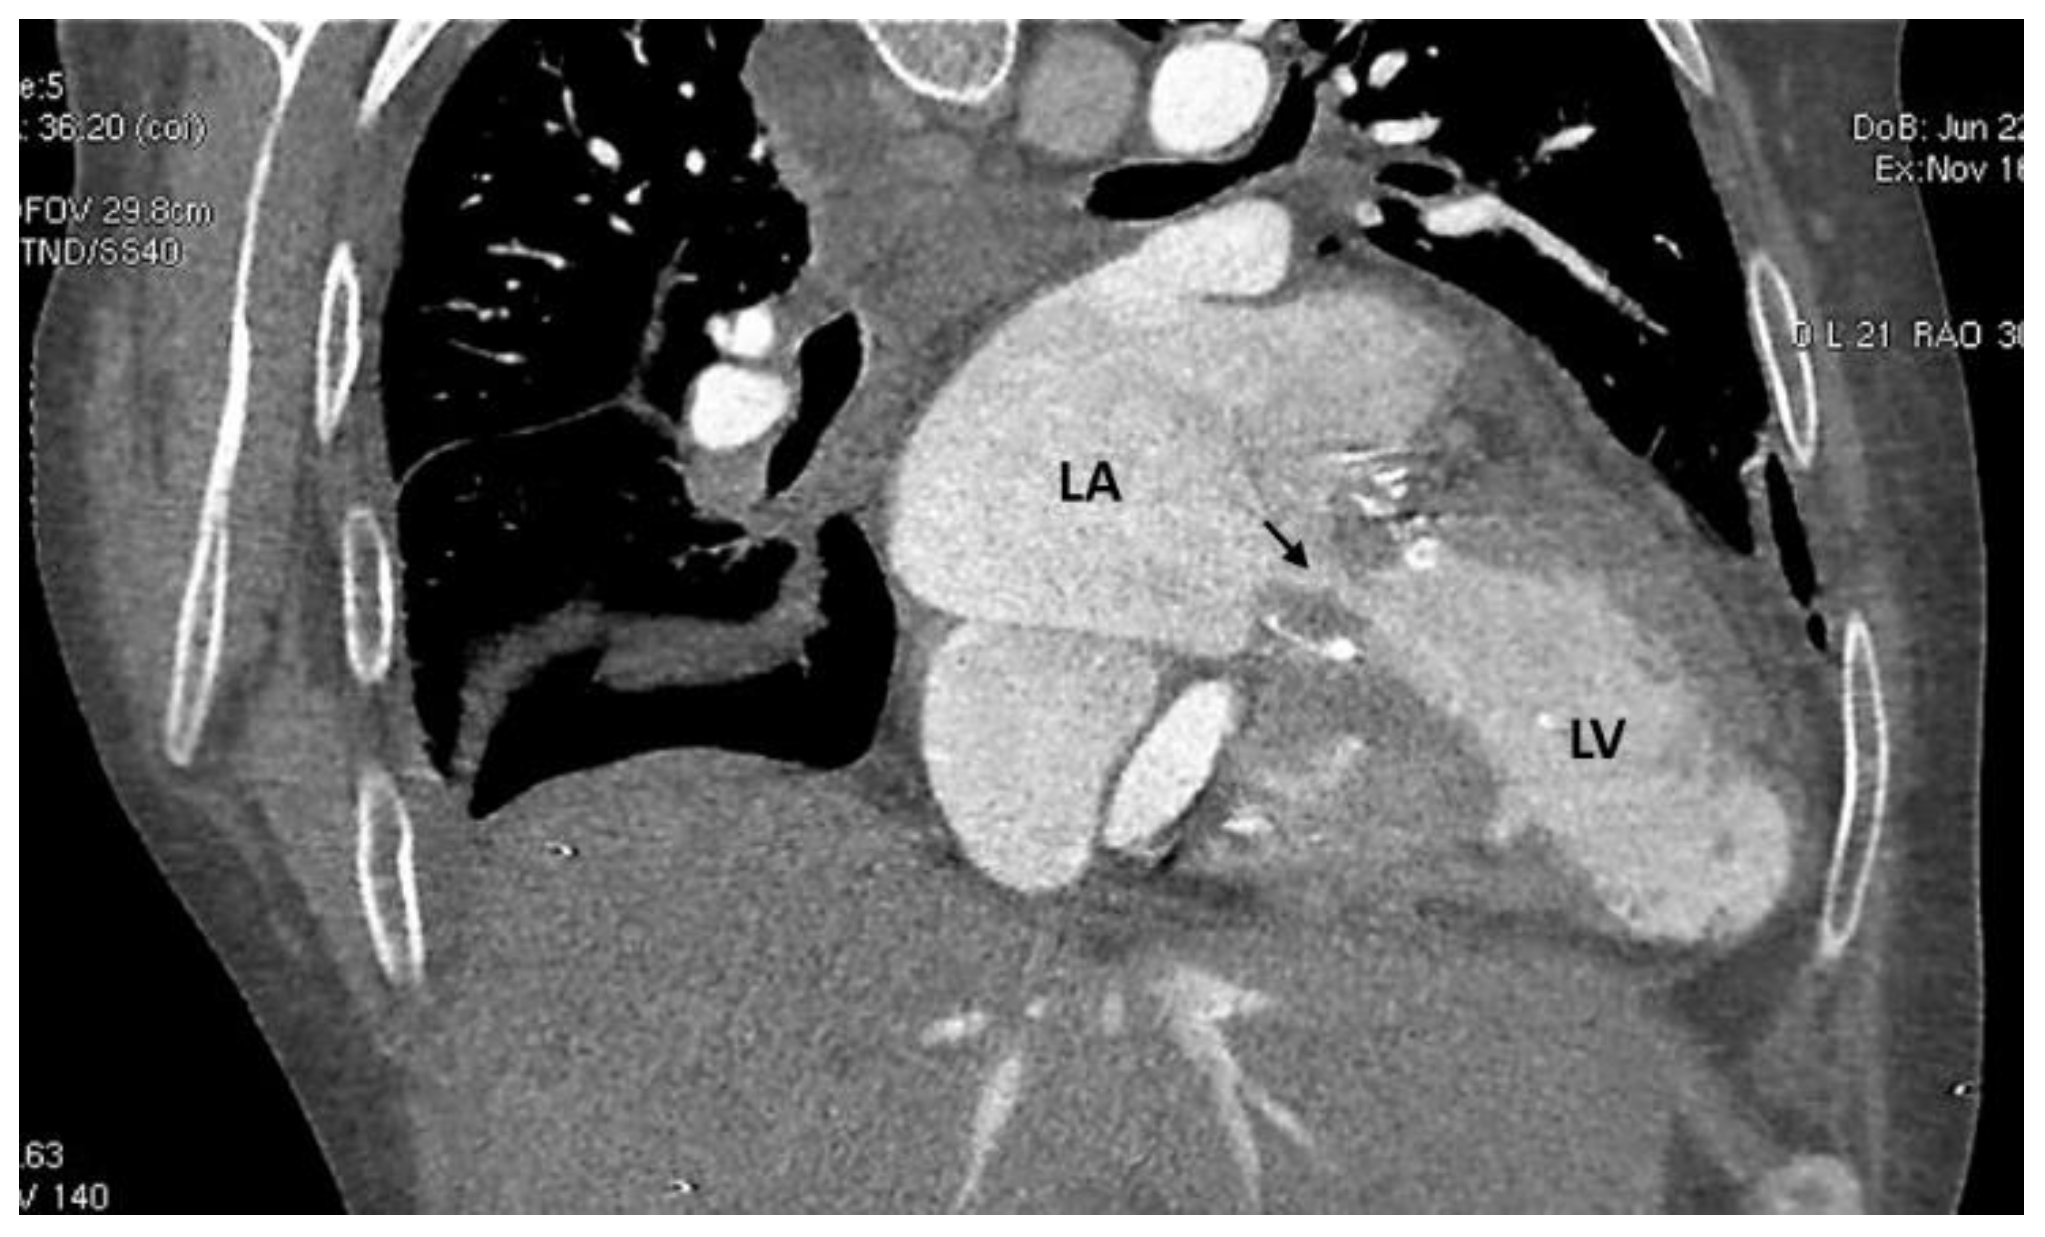

2. Case Description